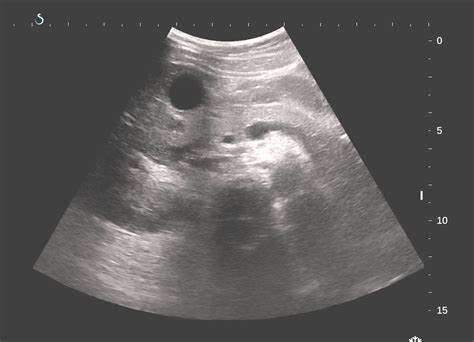

Murphy sign — a sign of gallbladder disease consisting of interruption of the patient s deep inhalation when the physician s fingers are pressed deeply beneath the right costal arch, below the hepatic. Murphy's sign is a physical exam finding in a patient presented with right upper quadrant pain or tenderness and can be suggestive of the cholecystitis. Murphys sign positive negative sonographic video ehealthstar. What is the most likely diagnosis? A positive sonographic murphy sign, the presence of maximal tenderness elicited over a sonographically localized gallbladder, has been reported to be a helpful adjunctive finding in patients.

It is elicited by firmly placing a hand at the costal margin in the right upper abdominal quadrant and asking. Murphy's sign is a physical exam finding in a patient presented with right upper quadrant pain or tenderness and can be suggestive of the cholecystitis. Murphys sign positive negative sonographic video ehealthstar. Murphys sign positive negative sonographic video ehealthstar. Sonographic murphy sign is the radiological correlate of the clinical murphy sign, which is elicited by deep palpation of the if the patient's breath abruptly stops, then it is a positive murphy sign 5,6. In elderly patients, a positive murphy sign is useful, but a negative sign is not exclusive and other diagnostic tests should be performed immediately. Clinical medicine pain on inspiration when the examiner's fingers are placed under the clinical manifestations were fever, right upper quadrant tenderness, and a positive murphy's sign. It is useful for differentiating pain in the right upper quadrant.

Position of gallbladder in abdomen. Common surgical presentations ppt download. A positive sonographic murphy sign, the presence of maximal tenderness elicited over a sonographically localized gallbladder, has been reported to be a helpful adjunctive finding in patients. Common surgical presentations ppt download. Murphy s sign rome fontanacountryinn com. To perform the test, palpate the gallbladder area medial to the midclavicular line while the. Murphy's sign may be even less accurate in elderly patients, because up to 25% of patients older than 60 years of age with cholecystitis lack any clinical: The ultrasound murphy sign is defined as. A positive sonographic murphy sign, the presence of maximal tenderness elicited over a sonographically localized gallbladder, has been reported to be a helpful adjunctive finding in patients. If the patient stops breathing in (as the gallbladder is tender and, in moving downward, comes in contact with the examiner's fingers) and winces with a 'catch' in breath, the test is considered positive. Typically, it is positive in cholecystitis, but negative in choledocholithiasis, pyelonephritis, and ascending cholangitis. These images are a random sampling from a bing search on the term murphy sign. A positive murphy's sign is seen in acute cholecystitis.

A positive sonographic murphy sign, the presence of maximal tenderness elicited over a sonographically localized gallbladder, has been reported to be a helpful adjunctive finding in patients. Murphy's sign is a physical exam finding in a patient presented with right upper quadrant pain or tenderness and can be suggestive of the cholecystitis. A test for gallbladder disease in which the patient is asked to inhale while the examiner's fingers are hooked under the liver what does it mean to have a positive murphy's sign? Palpate the right subcostal area while the patient inspires deeply. Murphys sign positive negative sonographic video ehealthstar. A positive sign is useful, however a negative sign is not reliable to rule out acute cholecystitis and further diagnostic tests should be. A positive murphy sign can be seen with acute cholecystitis. Murphy sign — a sign of gallbladder disease consisting of interruption of the patient s deep inhalation when the physician s fingers are pressed deeply beneath the right costal arch, below the hepatic. Position of gallbladder in abdomen. To perform the test, palpate the gallbladder area medial to the midclavicular line while the. These images are a random sampling from a bing search on the term murphy sign. Murphys sign positive negative sonographic video ehealthstar. In medicine, murphy's sign is a maneuver during a physical examination as part of the abdominal examination.